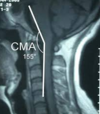

Power’s Ratio

Basion to posterior arch/Opisthion to anterior arch

Normal is 1

Abnormal: occipito-atlantal instability